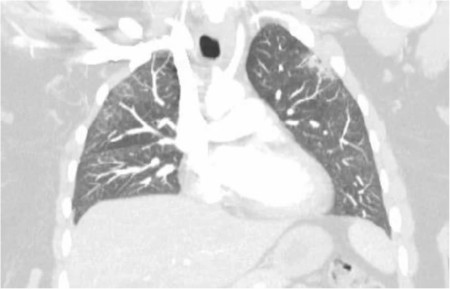

Clinicians describe a case report of a patient who initially presented with mild symptoms and stable vital signs. She returned 2 days later with worsening tachycardia and hypotension, and she had developed a pericardial effusion.

This case demonstrates that COVID-19 can affect multiple organ systems beyond respiratory complications. COVID-19, even though it enters the lung via angiotensin-converting enzyme 2, can also affect the heart and kidneys. Common COVID-19 presentations are still being elucidated, which highlights the importance of all presentations of the novel infection.